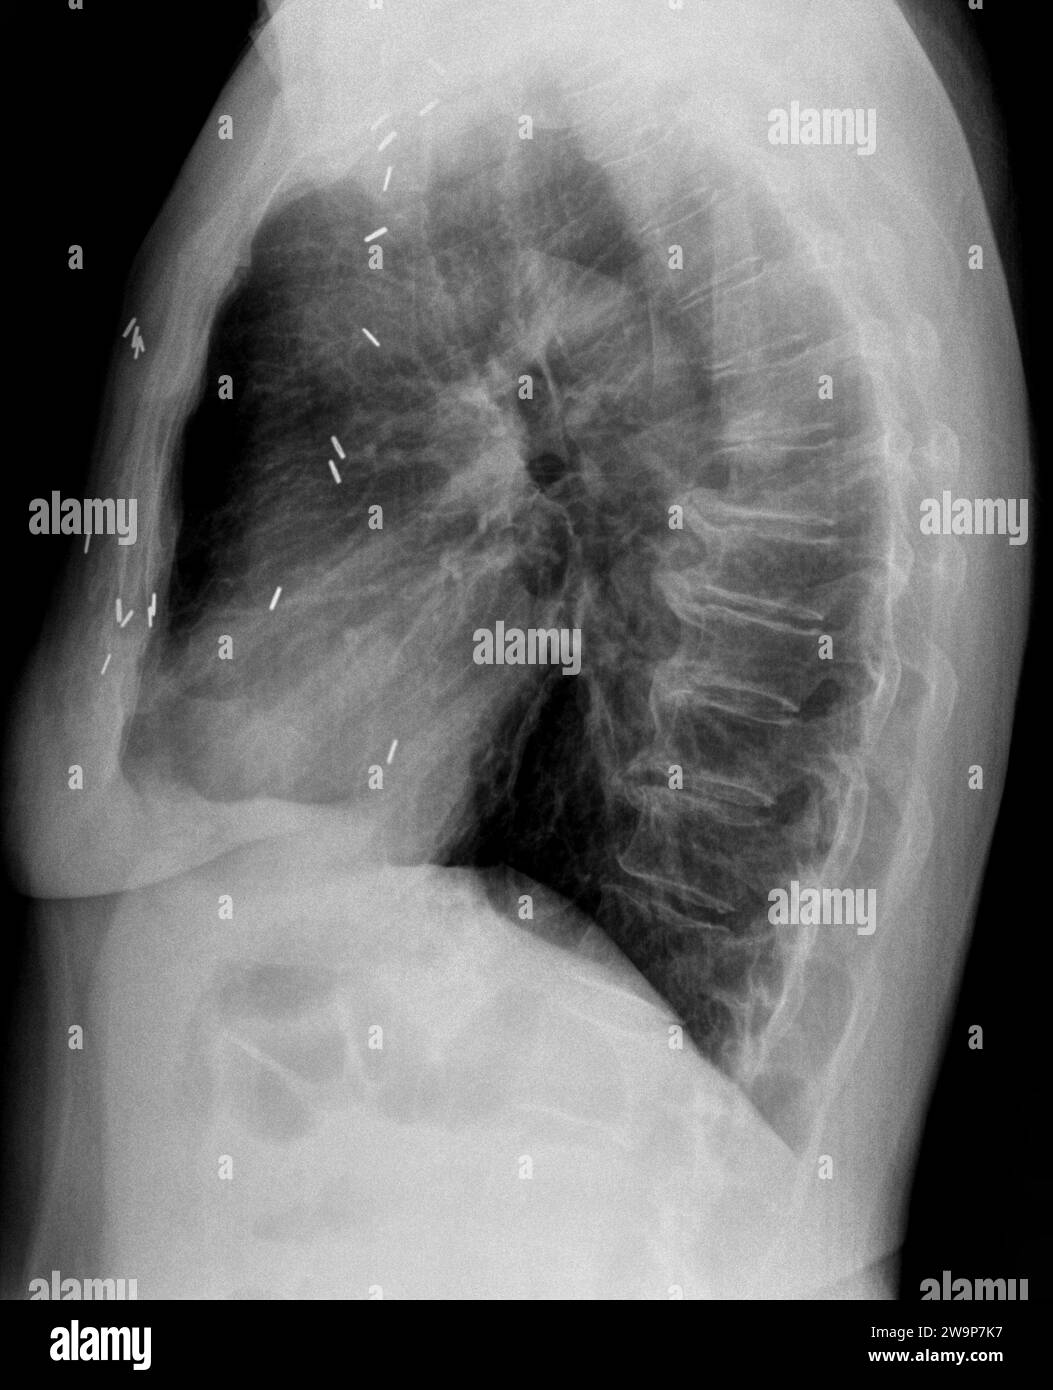

From www.alamy.com

Film xray or radiograph of a mid back thoracic vertebrae . Lateral side Staples Used In Lung Surgery Currently, staplers are widely used for clinical operations on the lungs, stomach, intestine, and pancreas as they improve operational efficiency and shorten surgery time, and are recommended for surgeons to use (baker et al., 2004; When compared with conventional products, slr could control. When it is difficult to decide which cartridge to use, selecting higher staple heights may reduce the. Staples Used In Lung Surgery.

From radiopaedia.org

Stapler line on chest xray after wedge resection Image Staples Used In Lung Surgery Manual surgical staplers currently play a dominant role in minimally invasive lung surgery, but disposable or not powered staplers. Surgical stapling devices offer a secure system of tissue approximation and are widely utilized for nonanatomic lung resections,. When it is difficult to decide which cartridge to use, selecting higher staple heights may reduce the risk of air leaks. The use. Staples Used In Lung Surgery.